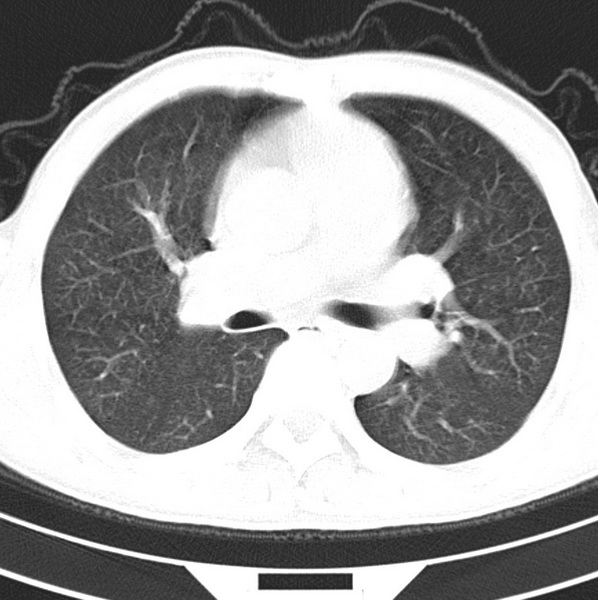

男、48、咳嗽。

胸片示双肺纹理紊乱,行胸部ct检查。

右肺下叶基底段结节影,双肺粟粒样阴影,ct值测量约-20hu左右,可能不准。

层厚层距为4mm左右,病灶轴面最大径约1cm左右。